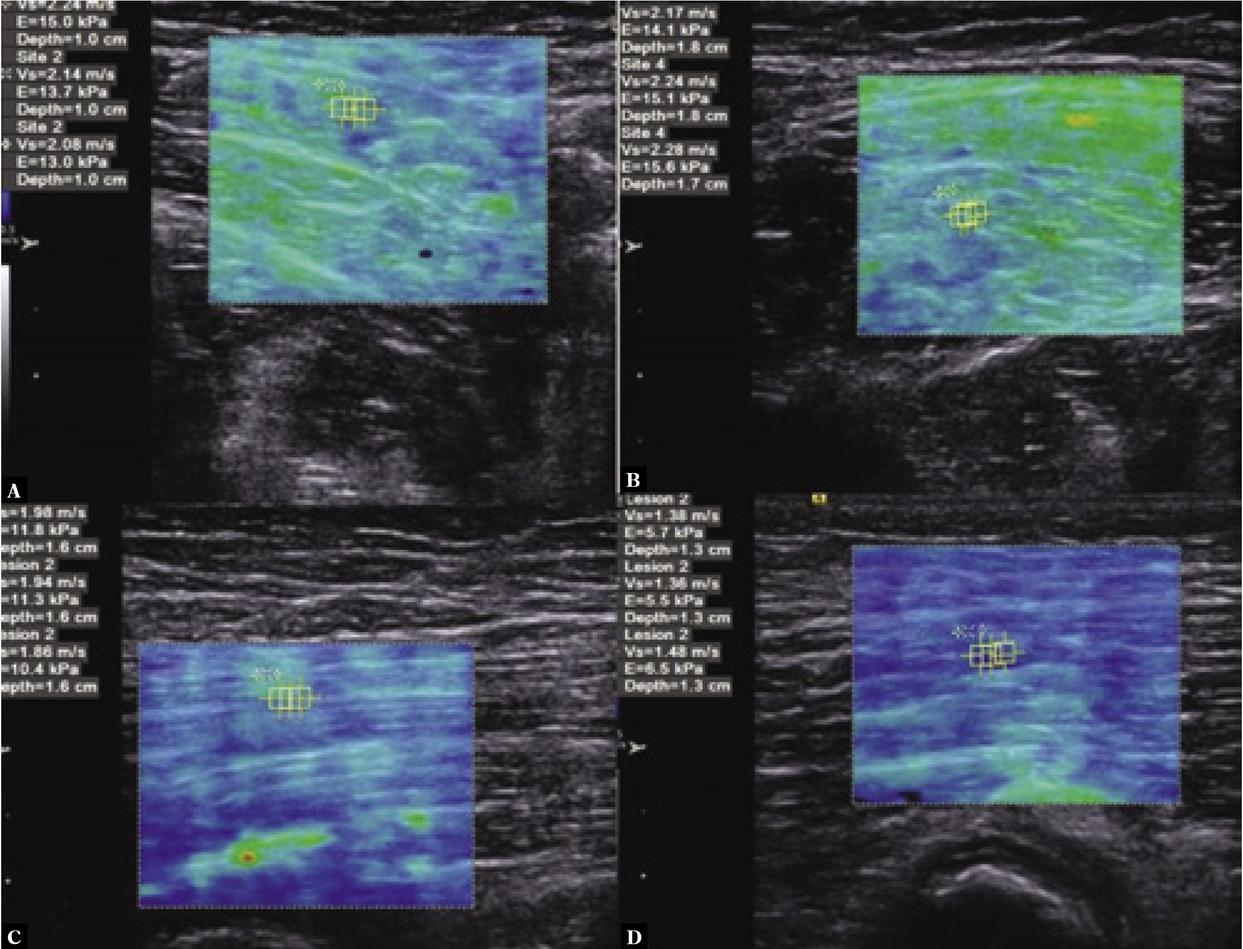

Fig. 1